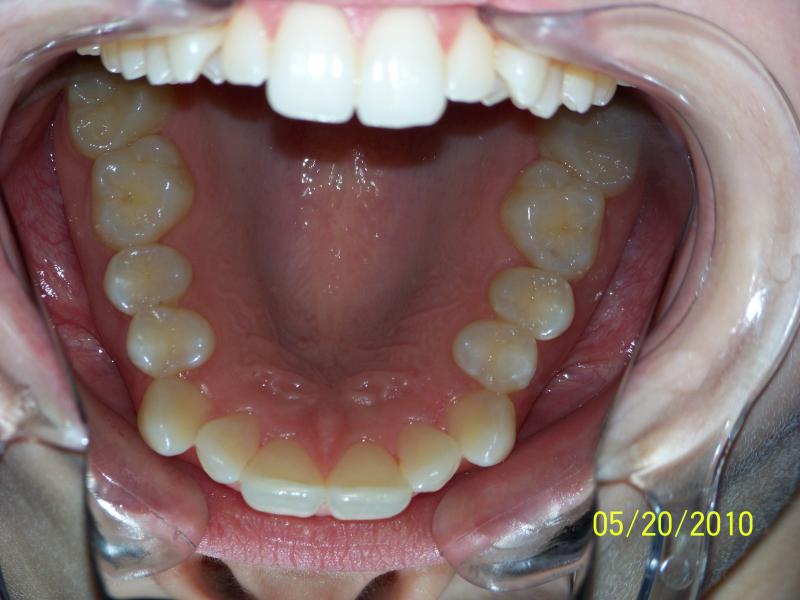

Isabelle G.

Invisalign Case

INVISALIGN, 10 months, 1 series of aligners to correct alignment, deep overbite and shift teeth to the right to match upper and lower mid line, TOTAL TREATMENT TIME: 10 months COSMETIC DENTISTRY: incisal reduction of anterior teeth before and after Invisalign.

Deep Overbite, Teeth Reshaping, Testimonial